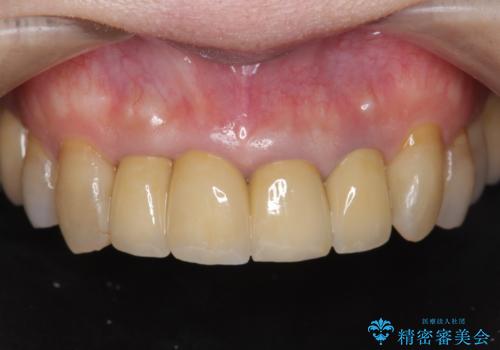

現在の歯ぐきの位置できっちりと仕上げることで見た目の改善が達成されました。

クラウン治療は経年的に歯ぐきの位置が変わり汚れが溜まってしまったり、見た目が悪くなるなどの問題が出てくることがあります。